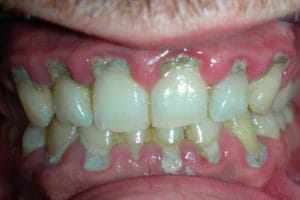

La tartrectomía (anglicismo de "tartar removal") consiste en la eliminación de cálculo dental o masa mineralizada adherida a los dientes para lograr una limpieza dental, con ultrasonidos e instrumentos odontológicos especiales.

- El raspado coronal o eliminación de cálculos supragingivales suele hacerse periódicamente (los odontólogos recomiendan una limpieza cada seis meses como profilaxis), para eliminar la acumulación de cálculo dental (sarro), depósitos blandos (placa dental) de difícil acceso o algunas manchas superficiales.

En el raspado coronal y radicular, la principal función es eliminar con ultrasonidos o instrumentación manual el sarro o cálculo dentario acumulado y toda la placa dental mineralizada y no mineralizada, fundamentalmente toda la masa acumulada en el borde gingival de las piezas dentales (supragingival) y en los espacios interproximales (entre los dientes). Esta acumulación de cálculos se produce a lo largo del tiempo y es inevitable aunque se puede retrasar con una correcta higiene dental. Sin embargo, existen espacios en la boca a los que ni siquiera un correcto cepillado es capaz de llegar y es por ello que con el tiempo el sarro se llega a formar inevitablemente como progreso de enfermedades como la periodontitis. Asimismo, esta acumulación se puede ver acelerada por diferentes factores como el tipo de bacterias en el biofilm microbiano, enfermedades bucales, estrés, predisposición genética y sobre todo, por la falta de una correcta higiene dental con cepillo, hilo y el uso rutinario de algún antiséptico antiplaca.